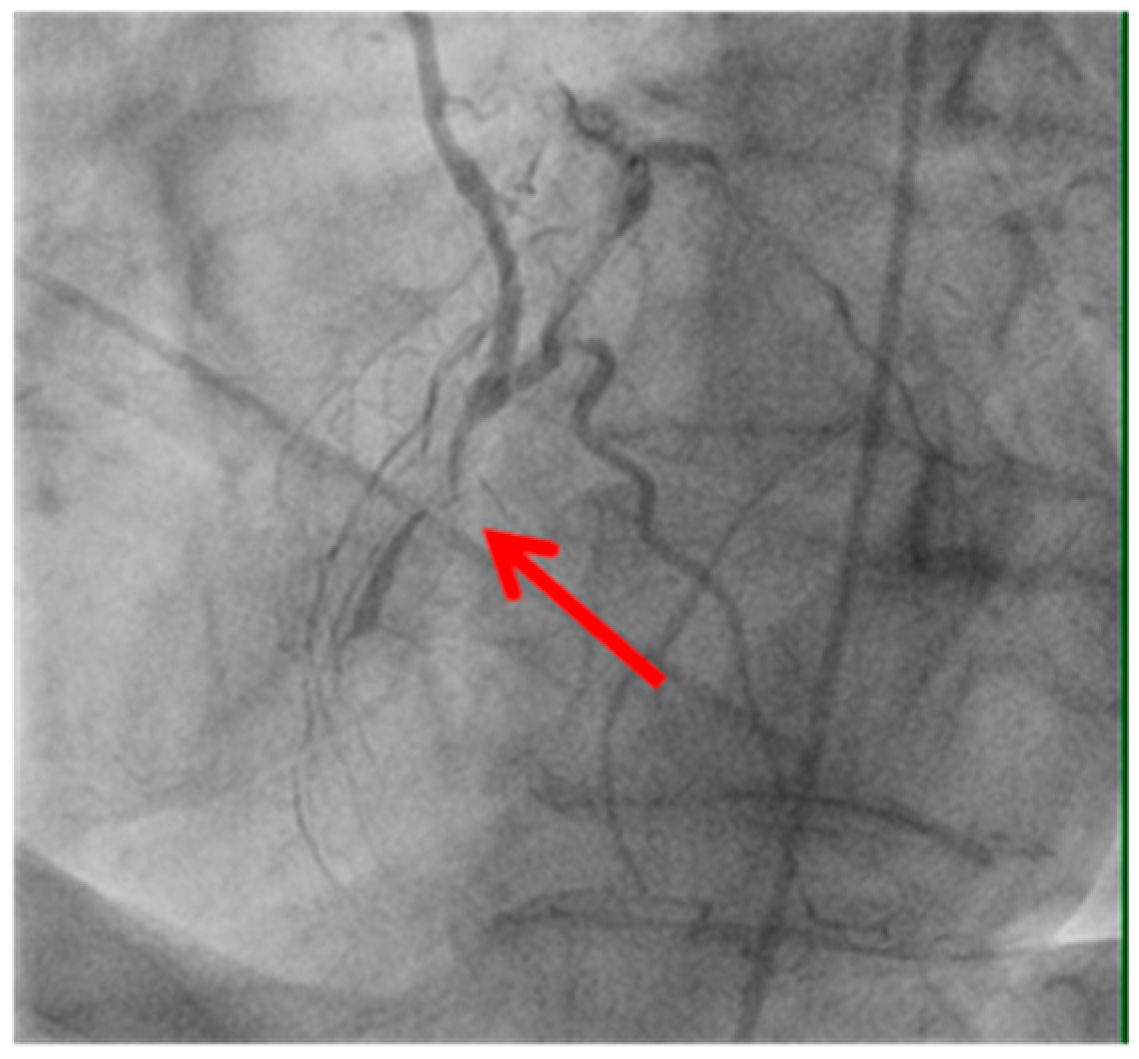

Technical issues remain a principal cause of PMI, with early graft thrombosis or occlusion being leading indications for uCAG (Figure 1, Figure 2, Figure 3 and Figure 4 illustrate typical technical causes, including proximal anastomotic stenosis, kinking, distal anastomotic stenosis, and misplaced anastomoses). Notable contributors include anastomotic stenosis, kinking, overstretching of grafts, and temporary graft spasm [13,21]. Prueßer et al. demonstrated that 30% of PMI cases detected via CAG were graft-related failures [13]. In this context, uCAG often reveals technical failures immediately post-surgery, providing the advantage of guiding targeted percutaneous coronary intervention or revascularization. Graft spasm, which can be relieved by nitrates, may also lead to acute ischemia. It refers to the temporary constriction of the bypass graft, reducing blood flow to the myocardium. This condition can be caused by various factors, including surgical trauma, inflammation, or the release of vasoactive substances [21].

Stenosis of the proximal anastomosis (shown by the red arrow) visualized on early postoperative coronary angiography. This image demonstrates a technical cause of early graft failure, which can lead to perioperative myocardial infarction if not promptly identified and treated.

Figure 1. Stenosis of proximal anastomosis.